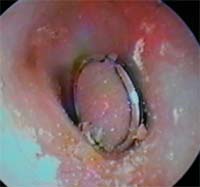

8歳6カ月(小学2年生) ビービー弾を左耳に 入れた 直径5.9mm 2018年5月23日  |